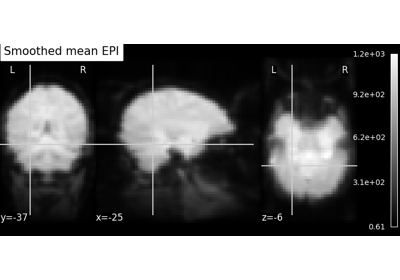

Exercise: Varying the amount of smoothing in an image

Compute the mean EPI for one individual of the brain development

dataset downloaded with nilearn.datasets.fetch_development_fmri and

smooth it with an FWHM varying from 0mm to 20mm in increments of 5mm

Intermediate steps:

Run

nilearn.datasets.fetch_development_fmriand inspect the.keys()of the returned objectCheck the

nilearn.imagemodule in the documentation to find a function to compute the mean of a 4D imageCheck the

nilearn.imagemodule again to find a function which smoothes imagesPlot the computed image for each smoothing value

A solution can be found here.